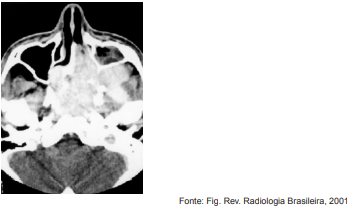

Adolescente, sexo masculino, 15 anos, iniciou com obstrução nasal unilateral e episódios de sangramento recorrentes de fossa nasal esquerda, em média, três vezes por semana. Submetido a exame tomográfico que evidenciou uma massa na nasofaringe com alargamento da fossa pterigopalatina à esquerda.

Analise a imagem abaixo.